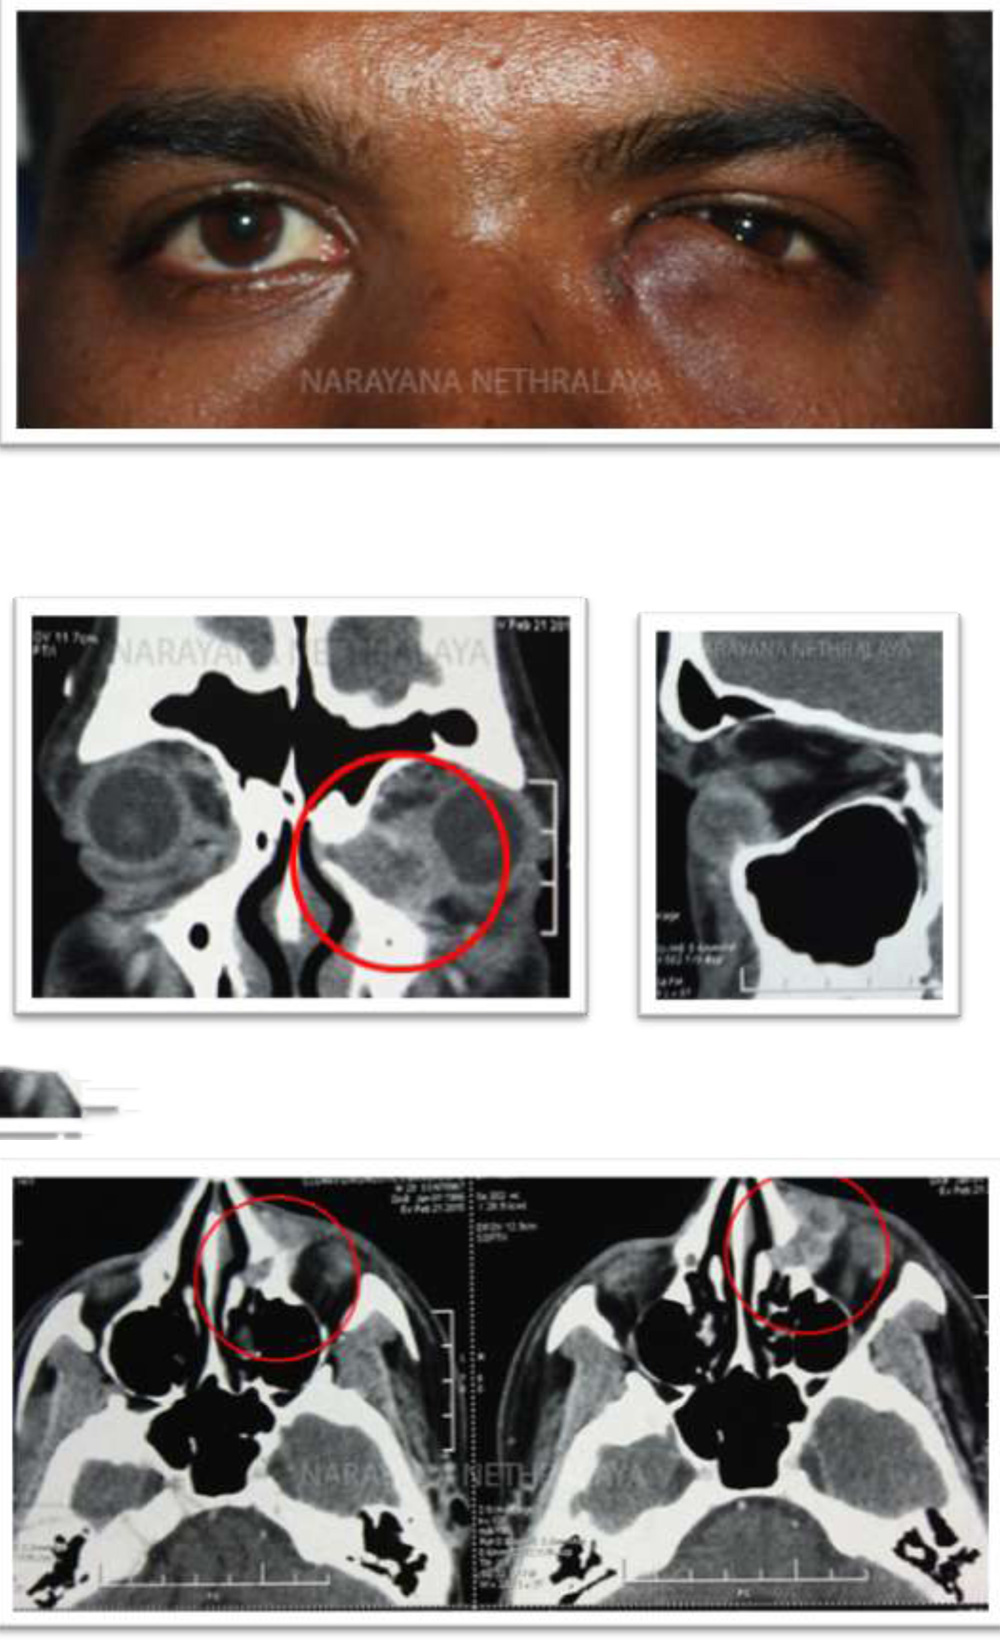

LEGENDS :

Figure 1:

Clinical photograph showing scar and induration in lacrimal sac area.

Figure 2,3,4:

Computerized Tomography of orbit showing heterogenous enhancing mass in left inferiomedial orbit, eroding into inferior meatus. Coronal , sagittal and axial sections respectively.

Clinical photograph showing mass above and below medial canthal tendon. Telecanthus can also be noted.

Figure 8,9:

Computerized tomography of orbit shows homogenous mass from sac area, extending into extraconal medial orbit scalloping the bone. Coronal and axial sections respectively.